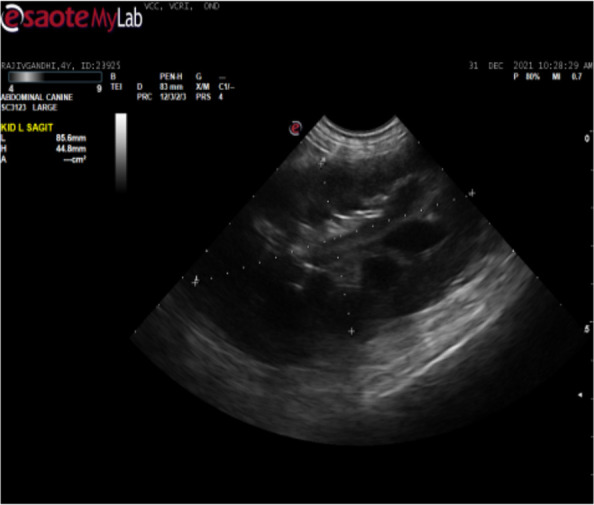

锥虫是红细胞外的血鞭毛原虫,寄生于包括狗在内的家养和野生动物体内。一只雄性罗威纳犬因厌食、眼睛浑浊和呕吐一周而就诊。对该犬进行了身体和临床检查。采集了血液并进行了血液学和生化分析。进行了胸腔超声心动图和腹腔超声波检查。通过 PCR 对寄生虫进行了分子确认,并对 DNA 进行了测序,以确定菌株变异。经临床检查,该犬消瘦,伴有高烧、单侧角膜混浊、贫血、淋巴结肿大和腹部膨胀。胸腔超声心动图显示心室肥大和心肌病。腹腔超声波检查显示脾脏肿大和肾脏肿大。血液学检查结果显示血红蛋白和红细胞计数下降,生化检查结果显示尿素氮和肌酐升高、低血糖和低白蛋白血症。湿片和血涂片检查分别显示锥虫运动活跃和锥虫大量感染。通过扩增 evansi 锥虫的 227 bp 部分 VSG 基因进行了分子鉴定,随后进行了测序和系统发育分析。感染犬在接受支持疗法的同时,肌肉注射醋酸地米那嗪(3.5 毫克/千克体重)。该研究描述了犬锥虫病的发生和诊断。早期诊断和及时治疗是保护伴侣动物的最可靠方法。这是印度泰米尔纳德邦考弗里三角洲地区首次报告犬锥虫病。

Trypanosomes are the extraerythrocytic haemoflagellate protozoan parasites of domestic and wild animals including dogs. A male Rottweiler dog was presented with the history of anorexia, cloudy eyes and vomiting for a week. The dog was examined both physically and clinically. Blood was collected and subjected to haematological and biochemical analysis. Echocardiography of the thoracic cavity and ultrasonography of the abdominal cavity were performed. Molecular confirmation of parasite was carried out by PCR and DNA was sequenced to identify strain variations. Upon clinical examination, the dog revealed emaciation with high fever, unilateral corneal opacity, anemia, enlarged lymph nodes and distended abdomen. Echocardiography of the thoracic cavity showed ventricular hypertrophy and cardiomyopathy. Ultrasonography of the abdominal cavity showed splenomegaly and renomegaly. Haematological findings revealed decreased haemoglobin and erythrocyte count and biochemical findings revealed increased BUN and creatinine, hypoglycemia and hypoalbuminemia. Wet film and blood smear examination revealed actively motile trypanosomes and massive infection of trypanosomes, respectively. Molecular confirmation of species was carried out by amplification of 227 bp partial VSG gene of Trypanososma evansi, subsequently sequenced and phylogenitically analysed. The infected dog was treated intramuscularly with diminazene aceturate @ 3.5 mg/kg b.wt along with the supportive therapy. The study described the occurrence and diagnosis of trypanosomosis in dog. Early diagnosis and timely treatment is the most reliable way to safeguard the companion animals. It is the first report on trypanosomosis in dog from Cauvery delta region of Tamil Nadu, India.